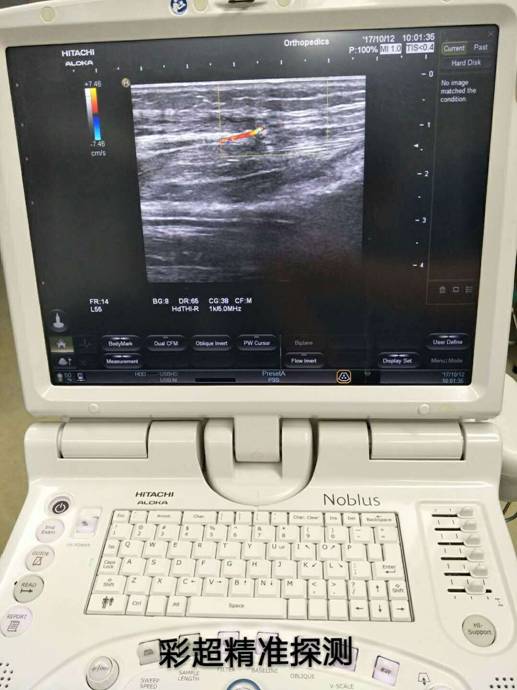

彩超定位精準治療骨折修復(fù)皮瓣

骨科根據(jù)患者骨折情況分別施行骨折復(fù)位+內(nèi)(外)固定術(shù),然后由燒傷整形科根據(jù)患者皮膚軟組織缺損情況,制定小腿穿支皮瓣轉(zhuǎn)移修復(fù)創(chuàng)面方案。為保證手術(shù)成功率,燒傷整形科會同超聲科由黃道遠主任于術(shù)前利用彩超精準的探測小腿術(shù)區(qū)的各個動脈穿刺,并逐一標記,再由燒傷整形科手術(shù)團隊根據(jù)動脈穿支的分布情況設(shè)計皮瓣,施行小腿穿支皮瓣轉(zhuǎn)移修復(fù)術(shù)。

由于采用了彩超定位技術(shù),使得皮瓣設(shè)計方案更合理,手術(shù)操作更精準,手術(shù)耗時更少,更因為保護好了血管,術(shù)后皮瓣腫脹,存活均較以往有明顯改善,手術(shù)效果得到極大保障,患者滿意度大大提高。